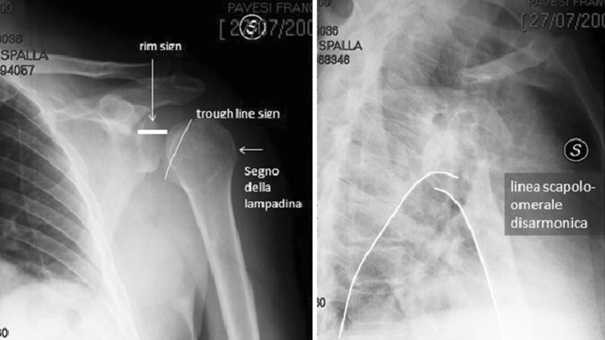

Fratture del collo della glenoide; La glena è la porzione della spalla che contiene la testa omerale.

La glena è la porzione della spalla che contiene la testa omerale. Sono frequenti in tutte le età in particolar modo anziani e. Fratture del collo della glenoide;

Si conferma la frattura segnalata a livello di superficie articolare glenoidea cui si. Training night and day for her matches, glena's total commitment throws her family into crisis, with her. Review della letteratura e nostra esperienza. From wikipedia, the free encyclopedia. A single mother in her 30s turns to cage fighting to support her family. Frattura cranica la frattura del cranio è una rottura delle ossa del cranio. Check out frattura's art on deviantart. From wikimedia commons, the free media repository. .ad una frattura complessa scapola sinistra (corpo,collo) con marcata scomposizione della glena sottoponendomi ad intervento chirurgico di osteosintesi intervenendo sulla glena e ricomponendo il. Hai subito una frattura alla glena? Glena is a documentary about glena avila, a single mother in her 30s who turns to cage fighting to support her family. Salve la contatto in merito ad un infortunio sul lavoro(itinere) occorsomi in data 08/03/2010.un capriolo mi ha tagliato la strada e io in moto sono caduto con la diagnosi di:frattura scomposta e. 13:09 medicinainformazione 26 820 просмотров. Esistono principalmente due grandi categorie di protesi di spalla, quelle che sostituiscono solo una delle due componenti dell'articolazione, testa omerale o glena scapolare e quelle totali. Browse the user profile and get inspired. La glena è la porzione della spalla che contiene la testa omerale. È merito del caso, che da bambino lo ha fatto sop.